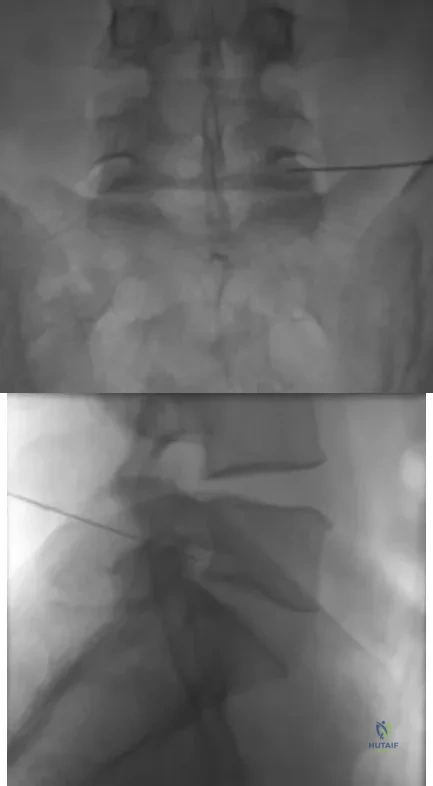

The injection shown in Figures 1a and 1b would most benefit a patient who reports which of the following symptoms?

Explanation